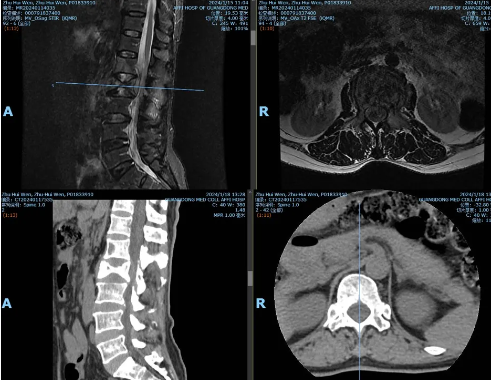

典型案例四

全麻下射频消融联合脊柱转移瘤分离手术

·患者朱某某,女,58岁,因反复腰背部疼痛半年,加重1周入院。腰背痛VAS评分7分。

·诊断:1.腰2椎体转移瘤(ESCC,2级);2.肺癌

智能控温射频消融能明显减少瘤体出血量(出血量50ml),为分离手术提供操作基础,降低输血依赖。分离手术实现充分减压,为后续放疗治疗提供可能性。